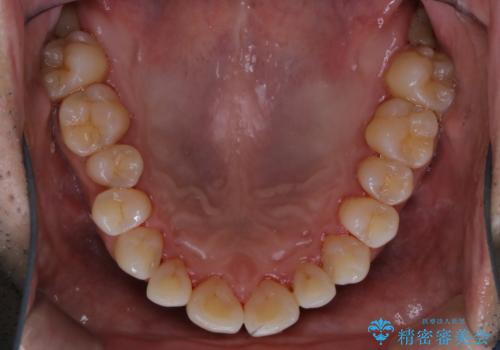

- 40年ほど歯科医院へ行ってなく、ザラつきがきになるとの事で来院されました。最近は普段の歯磨きの際、出血することがあり、歯ブラシ指導も希望されました。

お口全体に、歯垢・歯石が付着していたため、自費クリーニング(PMTC)60分コースを行い、徹底的に除去しました。

治療途中

終了時

40年ぶりの来院との事で全体的に、古くからの歯垢・歯石が硬く多く付着していたため、自費クリーニング(PMTC)60分1万円+TAXコースを行いました。

日々の磨き残しなどをそのまま放置すると、細菌が固まり硬い歯石になります。

歯石になってしまうと、とても硬く、歯ブラシで取り除くことが出来なくなります。

よって、歯科衛生士による専門的なクリーニングを定期的に行うことがとても大切です。